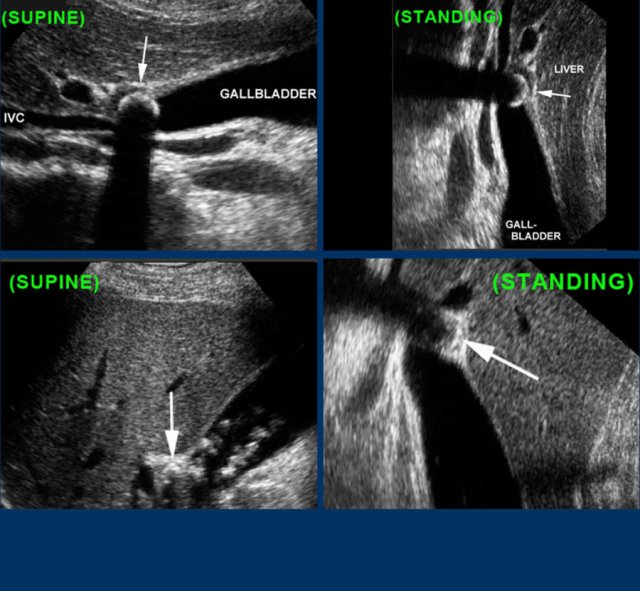

Here two examples of impacted stone visualized during biliary colic in different patients.

In the supine position a stone (arrow) is demonstrated in the gallbladder neck.

After standing up, bending over and walking, the stone (arrow) does not fall down, and therefore must be impacted.

Stones in the cystic duct are sometimes not demonstrable in the US plane of the longitudinal axis of the gallbladder.

Here images of a patieny with acute hydrops due to an impacted stone.

The impacted stone could not be visualized in the longitudinal axis of the gallbladder, due to its medial position in the cystic duct (arrow).